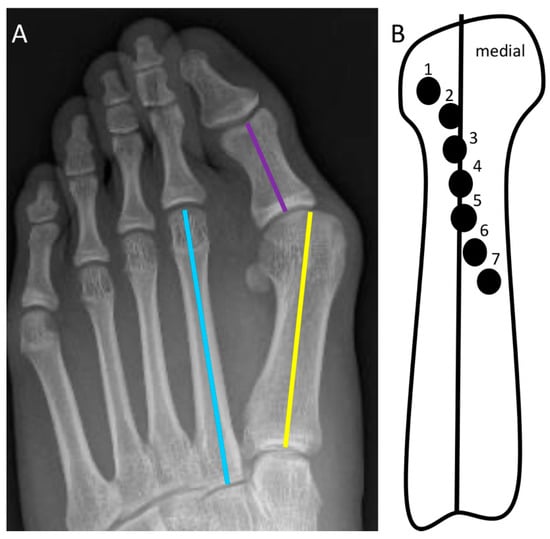

2.10. Second-Metatarsal Shortening

2.15. Medial Cuneiform Opening-Wedge Osteotomy